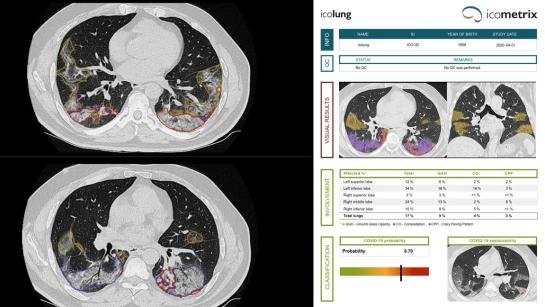

The Belgian initiative icovid, which supports radiologists in the assessment of CT images of the lungs of COVID-19 patients, has grown into a multicentre European project, co-funded by the EU Horizon 2020 programme.

The icovid project was launched in…